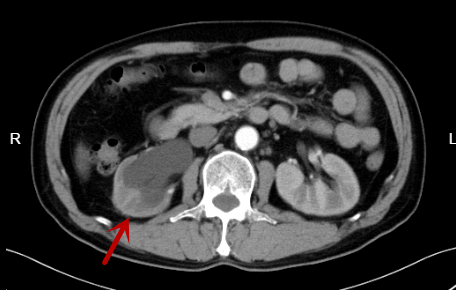

67岁的曾伯在外院体检时发现膀胱内有肿物,来我院门诊行CT检查提示右侧输尿管下段及膀胱右后壁占位,伴右肾大量积液。进一步膀胱镜检查可见膀胱右侧壁见肿物,大小约4*4cm,呈菜花状,活检结果提示尿路上皮癌,泌尿外科医生诊断考虑为输尿管恶性肿瘤合并侵犯膀胱。

CT检查提示患者右侧输尿管下段及膀胱右后壁占位